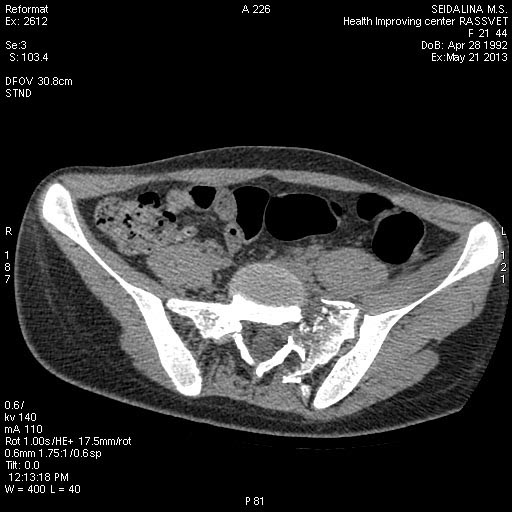

Сегодня мы имеем вот такой таз!Девушка 23г .Укорочение 4 см.

Давность травмы 5 нед, остеосинтез проведен к концу второй недели. КТ не получается отправить на диске, хитрая программа - не копирует. Вся боковая масса крестца, где илиосакральные винты, в мелких осколках. Перелом поперечного отростка 5 поясничного позвонка, в него так и упирается крыло. Неврологии нет.

КТ до операции.